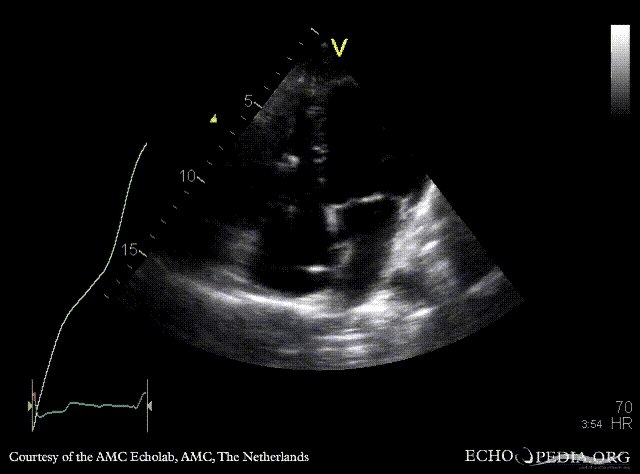

Aneurysm of IAS

AMC Echolab, AMC, The Netherlands

A4CH: aneurysm of IAS, "jump rope"